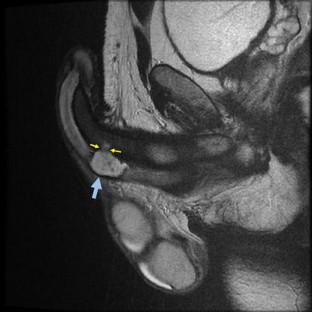

The “eggplant penis” sign

Fig. 1

• Corpus Cavernosa